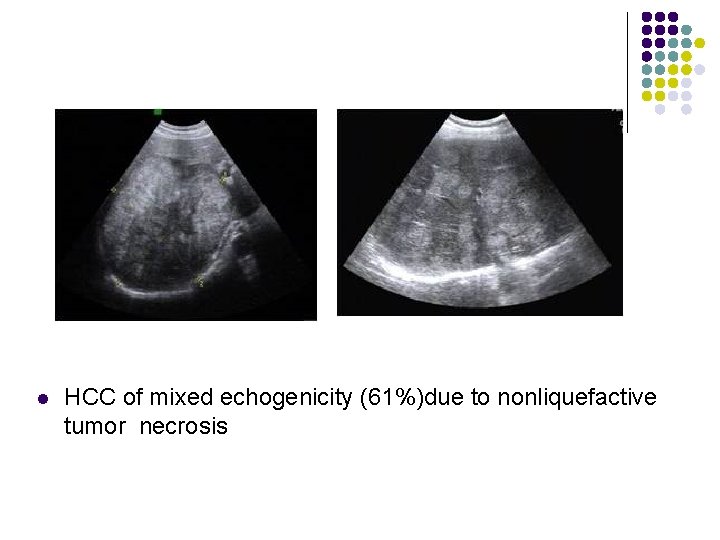

Sonographic Features of HCC l l l 86 -99% sensitivity; 90 -93% specificity; 65 -94% accuracy; Hyperechoic HCC(13%)due to fatty metamophosis or marked dilatation of sinusoids Hypoechoic HCC(26%)due to solid tumor HCC of mixed echogenicity (61%)due to nonliquefactive tumor necrosis

l HCC of mixed echogenicity (61%)due to nonliquefactive tumor necrosis